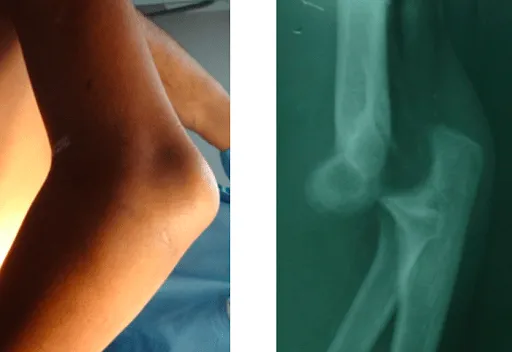

5. Trật khớp hoặc gãy xương vùng khuỷu

Một chấn thương ở khuỷu tay, chẳng hạn như té ngã khi cánh tay hoặc khuỷu tay dang ra, có thể gây trật khớp hoặc gãy xương. Trật khớp xảy ra khi xương di chuyển khỏi vị trí thông thường của nó. Gãy xương xảy ra khi xương có một vết nứt hoặc gãy.

Triệu chứng bao gồm:

- Thay đổi hình dáng khuỷu tay, gây sưng tấy.

- Đau khuỷu tay

- Không thể vận động khớp

Bác sĩ có thể nắn khớp trở lại vị trí, sau đó nẹp hoặc bó bột và cho bệnh nhân dùng thuốc để giảm đau và sưng. Sau khi tháo bột, người bệnh cần được vật lý trị liệu để phục hồi khả năng vận động.

- Khuỷu tay bị biến dạng rõ ràng, có thể nhìn thấy bằng mắt thường

- Xương lồi ra